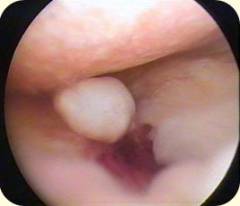

Артроскопия коленного сустава: ход операции

- Первым в полость коленного сустава вводят артроскоп. Хирург делает надрез на коже скальпелем, а затем прокалывает подкожный жир и суставную капсулу при помощи троакара, и попадает в полость сустава.

- Обычно вместе с основным проколом делают еще два. Через них можно ввести инструменты и канюлю для промывания сустава. Всего в области коленного сустава существует 8 точек, в которых могут быть сделаны проколы во время артроскопии.

- Врач последовательно осматривает все внутрисуставные структуры. При необходимости может быть проведена артроскопическая операция.